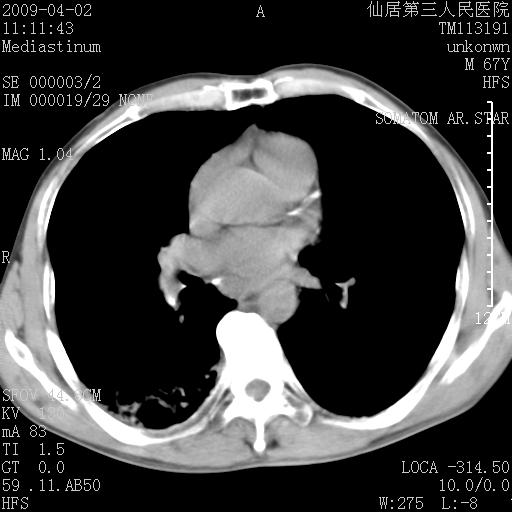

患者老年男性,乏力畏寒来诊,摄胸片示右下肺感染性病变,抗炎两周后复查胸片,无好转有进展。

后做ct平扫表现如下:

考虑右肺炎症可能性大,不除外细支气管肺泡癌

是否还要考虑肺间质纤维化,建议hrct扫描。

病灶呈蜂窝征,纵隔多个淋巴结肿大;肺泡癌需考虑

我认为普通的感染应该可以除外,间质性肺炎可能性较大,但如何解释纵膈的淋巴结肿大呢

考虑双肺间质性改变(间质纤维化?)伴右肺下叶感染。